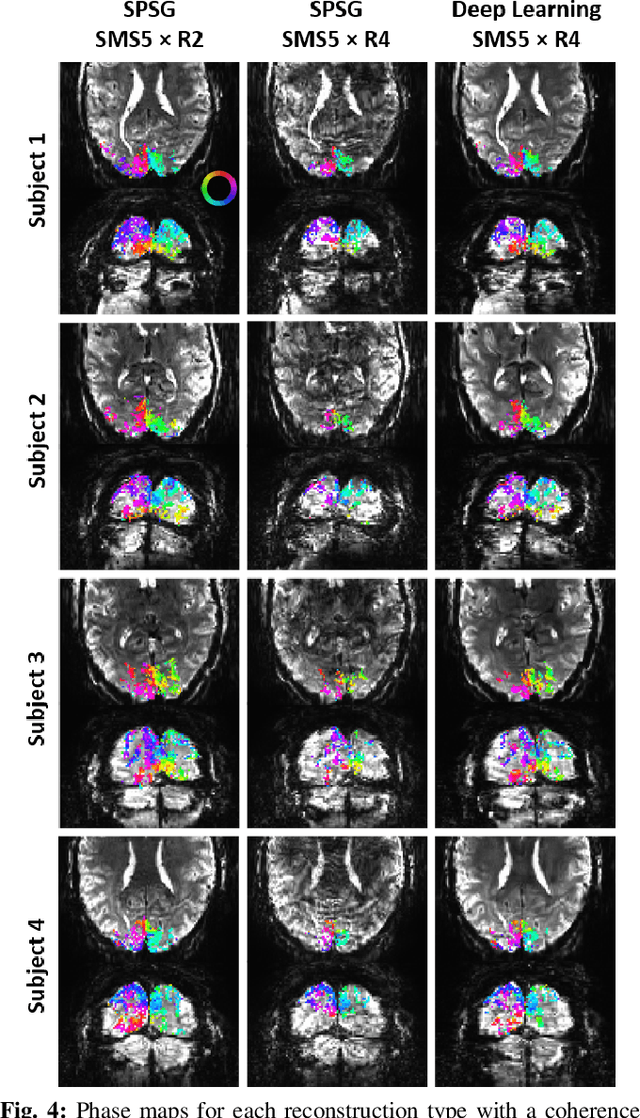

Abstract:High spatial and temporal resolution across the whole brain is essential to accurately resolve neural activities in fMRI. Therefore, accelerated imaging techniques target improved coverage with high spatio-temporal resolution. Simultaneous multi-slice (SMS) imaging combined with in-plane acceleration are used in large studies that involve ultrahigh field fMRI, such as the Human Connectome Project. However, for even higher acceleration rates, these methods cannot be reliably utilized due to aliasing and noise artifacts. Deep learning (DL) reconstruction techniques have recently gained substantial interest for improving highly-accelerated MRI. Supervised learning of DL reconstructions generally requires fully-sampled training datasets, which is not available for high-resolution fMRI studies. To tackle this challenge, self-supervised learning has been proposed for training of DL reconstruction with only undersampled datasets, showing similar performance to supervised learning. In this study, we utilize a self-supervised physics-guided DL reconstruction on a 5-fold SMS and 4-fold in-plane accelerated 7T fMRI data. Our results show that our self-supervised DL reconstruction produce high-quality images at this 20-fold acceleration, substantially improving on existing methods, while showing similar functional precision and temporal effects in the subsequent analysis compared to a standard 10-fold accelerated acquisition.

Abstract:Functional MRI (fMRI) is commonly used for interpreting neural activities across the brain. Numerous accelerated fMRI techniques aim to provide improved spatiotemporal resolutions. Among these, simultaneous multi-slice (SMS) imaging has emerged as a powerful strategy, becoming a part of large-scale studies, such as the Human Connectome Project. However, when SMS imaging is combined with in-plane acceleration for higher acceleration rates, conventional SMS reconstruction methods may suffer from noise amplification and other artifacts. Recently, deep learning (DL) techniques have gained interest for improving MRI reconstruction. However, these methods are typically trained in a supervised manner that necessitates fully-sampled reference data, which is not feasible in highly-accelerated fMRI acquisitions. Self-supervised learning that does not require fully-sampled data has recently been proposed and has shown similar performance to supervised learning. However, it has only been applied for in-plane acceleration. Furthermore the effect of DL reconstruction on subsequent fMRI analysis remains unclear. In this work, we extend self-supervised DL reconstruction to SMS imaging. Our results on prospectively 10-fold accelerated 7T fMRI data show that self-supervised DL reduces reconstruction noise and suppresses residual artifacts. Subsequent fMRI analysis remains unaltered by DL processing, while the improved temporal signal-to-noise ratio produces higher coherence estimates between task runs.